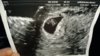

Miekin meen huomenna ultraan.. Soitin neuvolaan siitä perjantain verihyytymästä ni pääsin sitä kautta ultraan. Tosi tyytyväinen oon ettei tarvinnu yksityiselle mennä, ku monta sataa kuitenkin joka kuukausi veroja maksan ni pitäis kyllä miun mielestä päästäkin kunnalliselle. Huomenna siis 6+0, sano et on siinä ja siinä näkyykö syke, mut oli sitä mieltä et jos se keskenmeno ois tosiaan tapahtunut ni sen saattais sieltä nähdä, mut todennäköisesti viikon päästä ultraan vielä uudestaan.

Hui kun pelottaa:arghh: